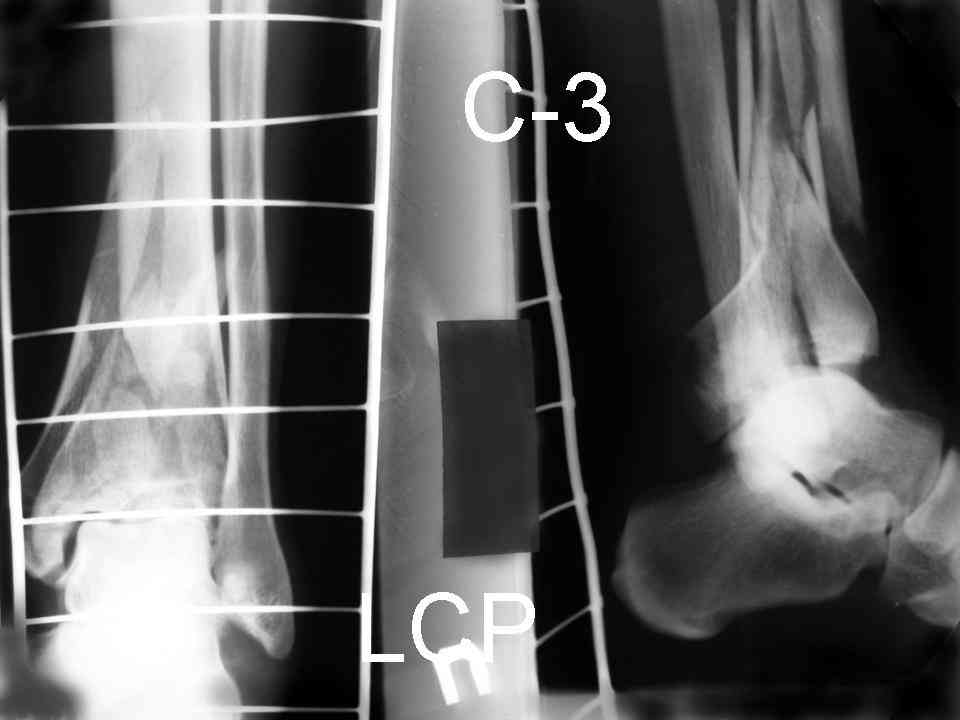

Это типичный перелом пилона, который надп лечить только открыто.Извини те что опоздал к обсуждению, но даже если вы уже оперировали больного по Илизарову это даже лучше.Посылаю картинки.

Посмотрим вроде прошло если понравится напишите расскажу как это сделать.По принципам АО кстати при поступлении сначала восстанавливают длину малоберцовой кости фиксируют пластиной 1/3 трубки потом накладывают аппарат наружной фиксации и через 7-10 дней открыто восстанавливают большеберцовую кость.С уважением Дрягин

На рентгенограммах типичный перелом пилона по типу С-3. есть опыт до 100 открытых опреаций у нас в клинике. 20 примерно в год. Принцип один -все внутрисуставные переломы нуждаются в открытой репозиции и внутренней стабильной фиксации. При поступлении КТ не надо, так как получается только нагромождение костей. Истинной картины нет. Главное восстановить длину малоберцовой кости - это ключ к успеху. При поступлении меньше всего надо думать о сосудистых расстройствах, т.к. сама операция и репозиция даже сначала частичная даёт улучшение сосудитых нарушений. Причём очень быстро. Операция в 2этапа. При поступлении доступ позади наружной лодыжки, причём обязательно. После этого репозиция малоберцовой кости и фиксация пластиной 1/3 трубки под винт 3,5. Дренаж и любой аппарат наружной фиксации. Затем после спадения отёка на 5-7-10 день аппрат снимается и дугообразный разрез спереди от медиальной лодыжки 10-12 см. Главной чтобы расстояние между 1 и вторым разрезом было не меньше 7-8 см. Тогда не будет некрозов лоскутов. Таранная кость используется как матрица на неё укладываются отломки и фиксируются пицами. Ренг-контроль. Отломки лежат все отдельно, но ничего не высыпется. При переломах С-3 всегда нужна костная пластика (из крыла). Фиксация пластиной лист клевера простой или LCP. Гипс не нужен. Дренаж до 48 часов. Операция длится 3-4 часа обязательно без жгута. Посылаю примерно такой же случай.

Посылаю результат лечения предыдущего больного через год.